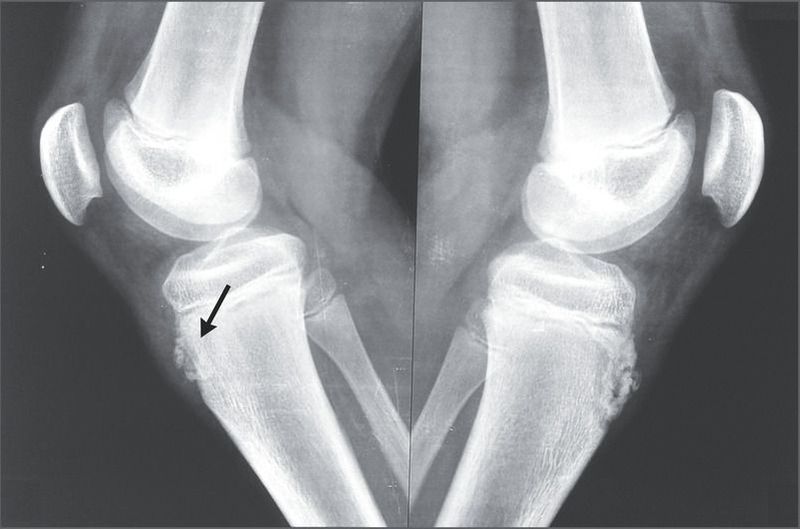

A 13-year-old boy presented to the orthopedic clinic with a 1-week history of pain in both knees. He was active in sports and had participated in the long jump during the previous 6 months. He reported no specific trauma, fever, or other joint symptoms. A physical examination of the right knee showed mild soft-tissue swelling and tenderness over the tibial tubercle, and the right quadriceps muscle was taut. The left knee was normal. Plain radiographs of both knees, which were obtained to rule out an avulsion fracture given the patient’s history of participation in the long jump, showed sclerosis and fragmentation of the tibial tubercle in both knees, with soft-tissue swelling on the right knee (arrow). These characteristic findings led to a diagnosis of Osgood–Schlatter disease, or osteochondrosis of the tibial tubercle, caused by repetitive traction of the patellar tendon at its attachment on the tibial tubercle. Osgood–Schlatter disease typically occurs during the early adolescent growth spurt between 10 and 15 years of age, particularly in children who participate in sports that involve running and jumping. Most cases resolve with supportive treatment. The patient received treatment with ice and nonsteroidal antiinflammatory drugs and was provided with instructions for stretching and strengthening exercises for the quadriceps and hamstring muscles. At a follow-up visit 3 weeks later, the patient reported less pain but stated that he chose not to resume participation in the long jump.